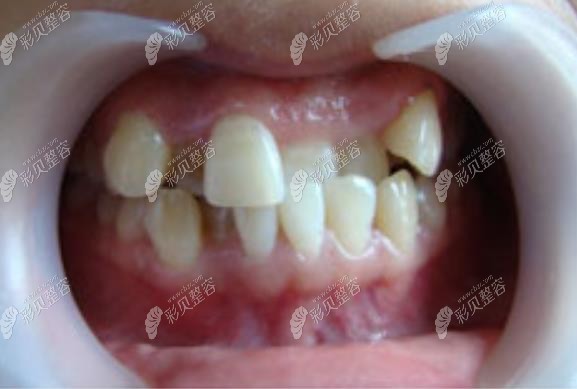

而我,很不幸,既有前牙错列,又有咬合错位,所以术前照是酱紫的。